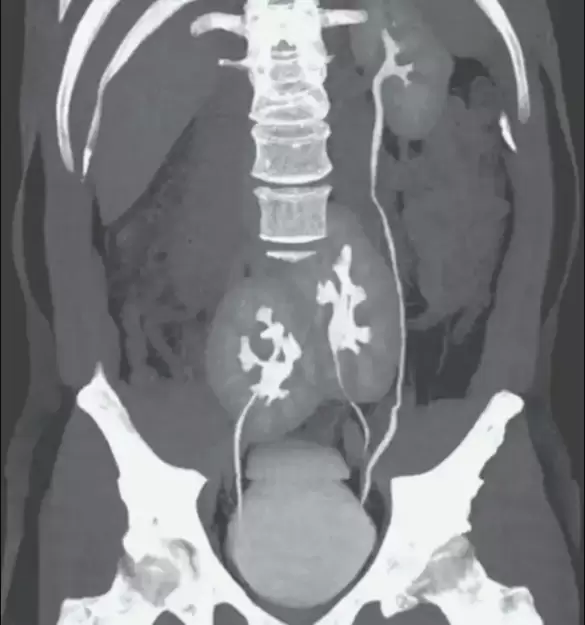

La imagen obtenida a través del estudio reveló que el paciente poseía tres riñones en lugar de dos, uno izquierdo que aparentaba ser normal y dos que se encontraban fusionados.

Según el medio Gizmodo, el doctor Renato Foresto, uno de los especialistas a en el Hospital Do Rim en la ciudad brasilera, explicó: “Nunca habíamos visto algo así. Fue una sorpresa, seguida de preocupación de que hubiera algo mal con la salud del paciente”.

“Sin embargo, y por extraño que parezca, la condición del hombre no parecía afectar su salud. Los análisis de sangre mostraron que su función renal era normal y, a excepción de una hernia discal, parecía estar bien. Se consideró suficiente investigación adicional con ultrasonido abdominal y tomografía ya que la causa del dolor ya había sido diagnosticada y no había otros cambios en las pruebas de laboratorio”, agregó.

En el informe, los médicos comentaron que las circunstancias del paciente se tratan de una anormalidad congénita poco común. Además, aclararon que, probablemente, sea el resultado de un desarrollo embrionario en el que una estructura primitiva similar de un riñón se haya dividido en dos.